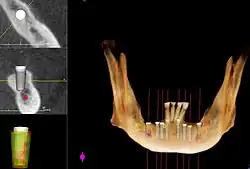

Методы, используемые для планирования имплантатов

Чтобы помочь хирургу позиционировать имплантаты, сделана направляющая (обычно из акрила), чтобы показать желаемое положение и угол наклона имплантатов.

Иногда окончательное положение и восстановление зубов будут смоделированы на гипсовых моделях, чтобы помочь определить количество и положение необходимых имплантатов.

Компьютерная томография может быть загружена в программное обеспечение CAD/CAM для создания симуляции требуемой обработки. Затем устанавливаются виртуальные имплантаты и на данных 3D-принтер создаётся стент.